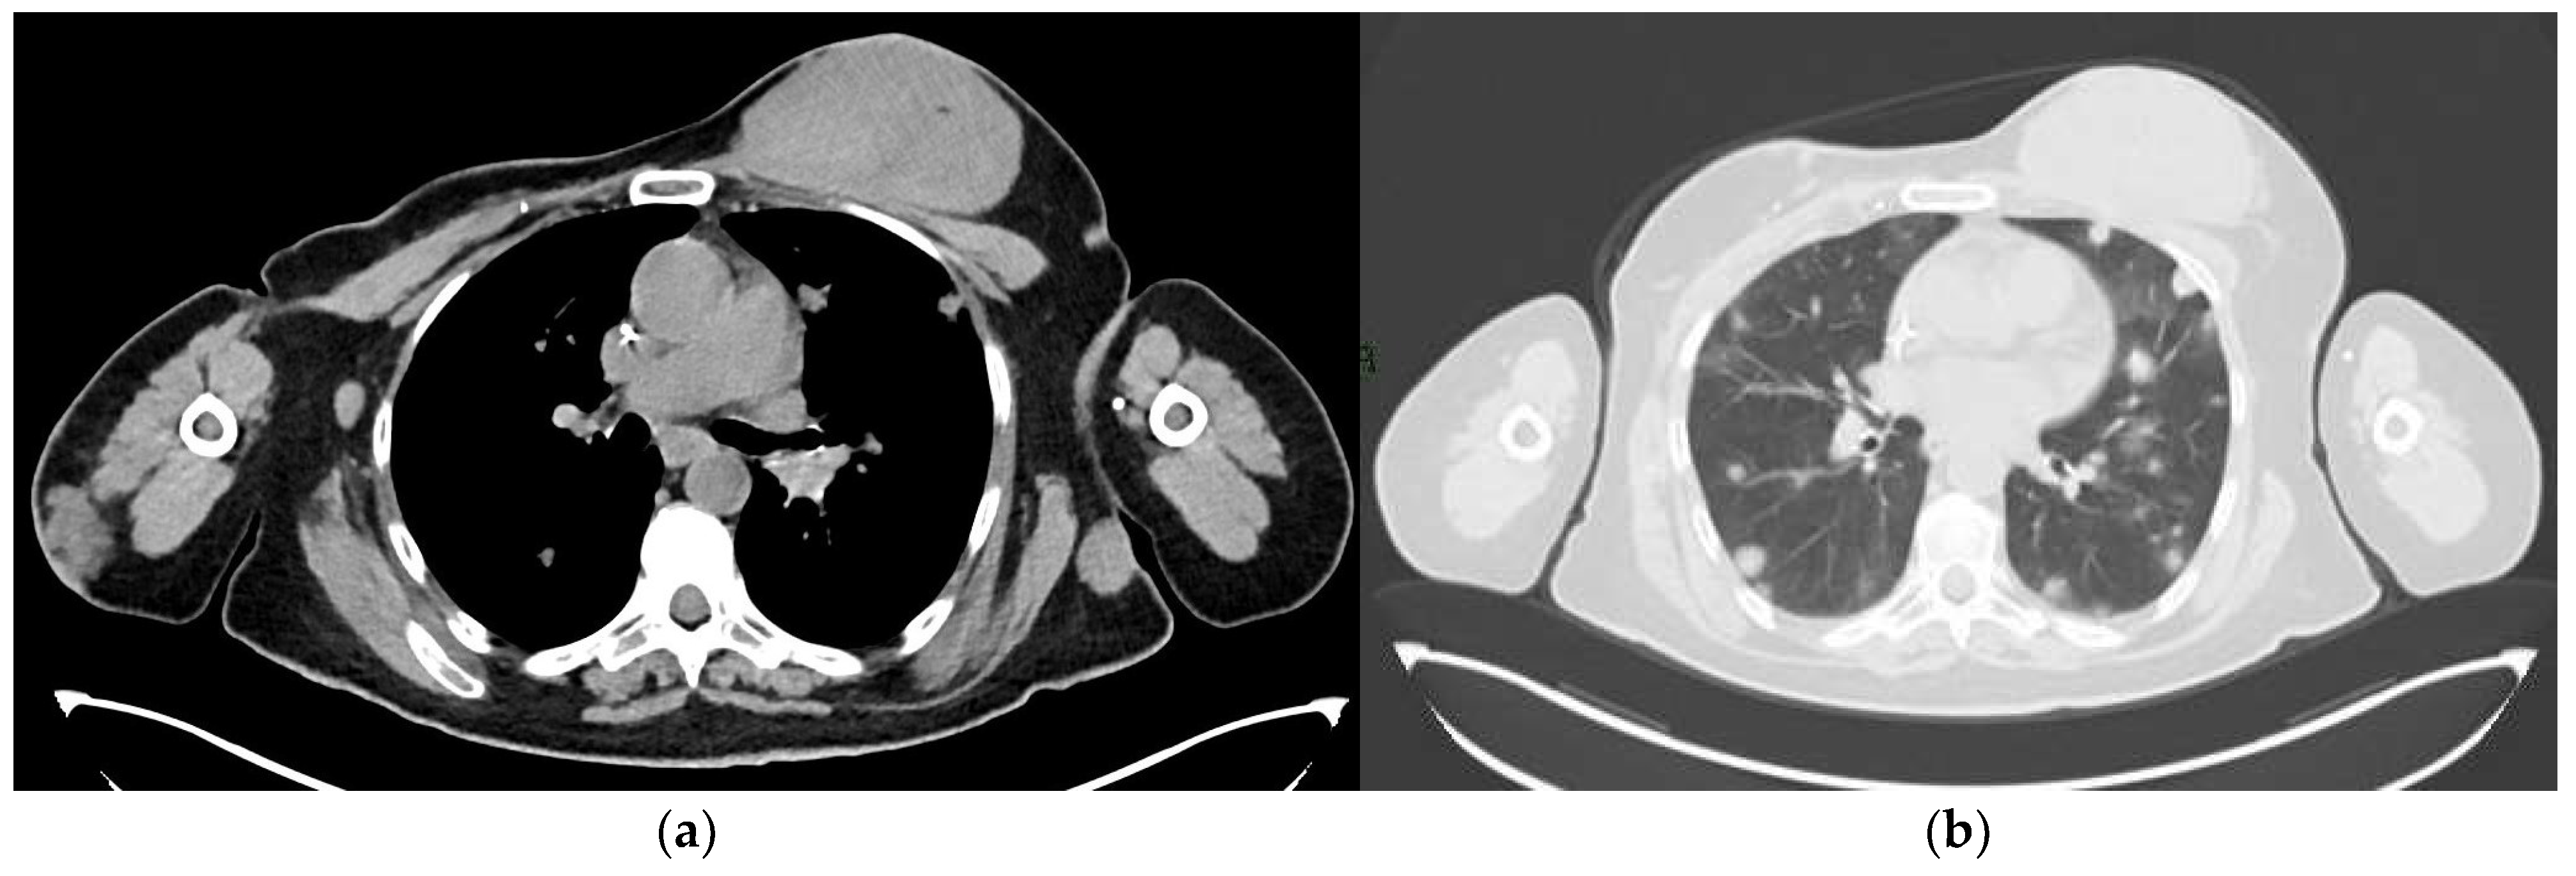

4.4. Computed Tomography